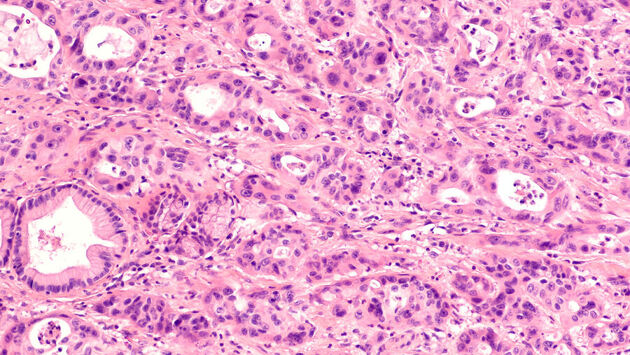

Результаты показали, что у мышей, которые продолжали питаться жирной пищей, быстрее появлялись признаки раннего рака поджелудочной железы и наблюдался прирост лишнего веса. В то же время у грызунов, сменивших рацион, вес нормализовался, и риск развития предраковых изменений снизился.